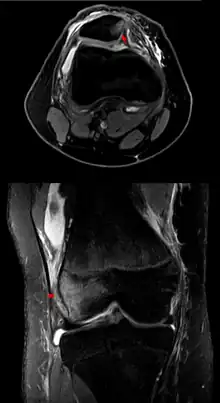

MRI after luxation of the right patella: A bone bruise is at the medial surface of the patella (axial image) and in the corresponding surface of the lateral condyle of the femur (coronal). The medial retinaculum of the patella is at least partially disrupted.